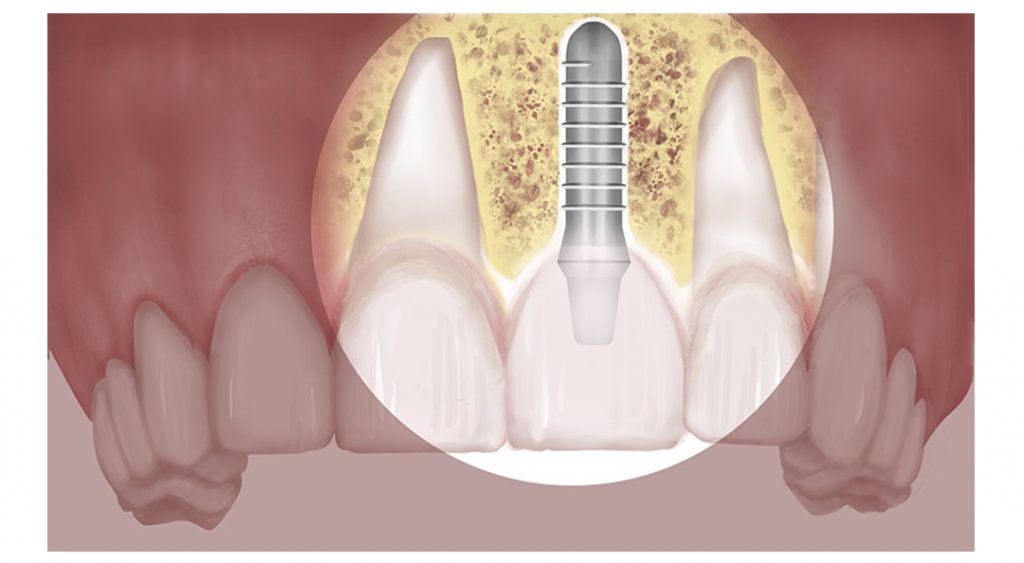

What Is A Sinus Lift And Bone Graft . Dental implants require a certain amount of bone for support, and surgically “lifting” the sinus floor makes more room for new bone to be grafted. People who have limited bone to secure a dental implant may need a sinus lift. sinus lift, or sinus augmentation surgery, adds bone to your upper jaw to make it taller. It takes about 6 months to fully heal. Sinus lift surgery is typically performed when there is not enough bone in the upper jaw, or the sinuses are too close to the jaw, to receive dental implants. sinus lift surgery is a dental procedure used when the existing rear upper jaw (maxilla) bone is insufficient for dental implants. a sinus lift, also known as sinus augmentation or sinus elevation, is a surgical procedure that adds bone to the maxillary. a sinus lift, also known as sinus augmentation, is a surgical procedure that aims to increase the amount of bone in. sinus lift surgery is an oral procedure to extend the upper jawbone into the maxilla sinus cavity with a bone graft. Sinus lifts specifically address bone deficiency in the upper jaw, particularly in the molar and premolar regions affected by the. a sinus lift, sinus augmentation, or sinus floor elevation is a common procedure to prepare someone for dental implants. To reinforce this area, oral surgeons graft harvested or synthetic bone into a space created by lifting the bone matter into the sinus cavity above the mouth.